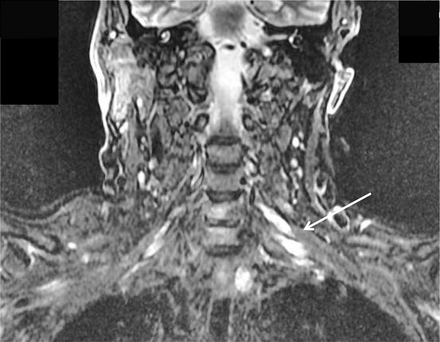

一位68岁的男子抱怨多年来左臂不协调、虚弱。临床检查显示假性震颤和轻微的左臂整体无力,袜子模式振动和针刺不敏感,只有轻微的左手本体感觉障碍首页®网址:首页Neurology.org).神经传导研究显示感觉电位普遍缺失或严重减弱,上肢多处运动传导阻滞(图1).MRI显示左臂丛神经根及干不对称扩大(图2).慢性炎性脱髓鞘性多神经根神经病可引起震颤,1但多灶性获得性脱髓鞘感觉和运动神经病,2不对称形式,尚未报道引起假手足徐动症。

图1

尺正中运动神经传导

正中和尺侧运动传导阻滞分别刺激肘关节和腋窝。Ae =肘部以上;Ax =腋窝;在肘部以下;E =肘;M =中位数;Sc =锁骨上;U =尺骨;W =手腕。